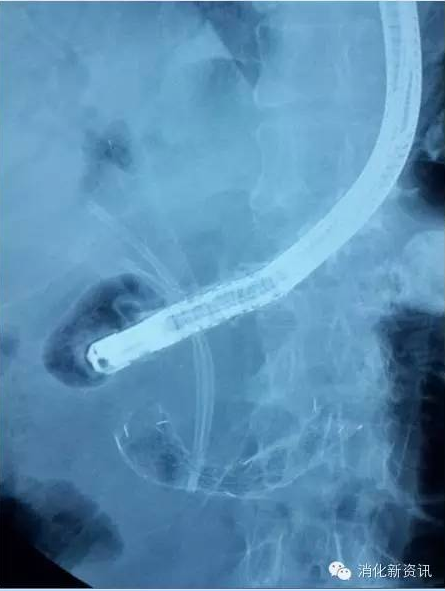

下图是十二指肠和胆管同时受阻,置入胆管支架和十二指肠支架的图片。